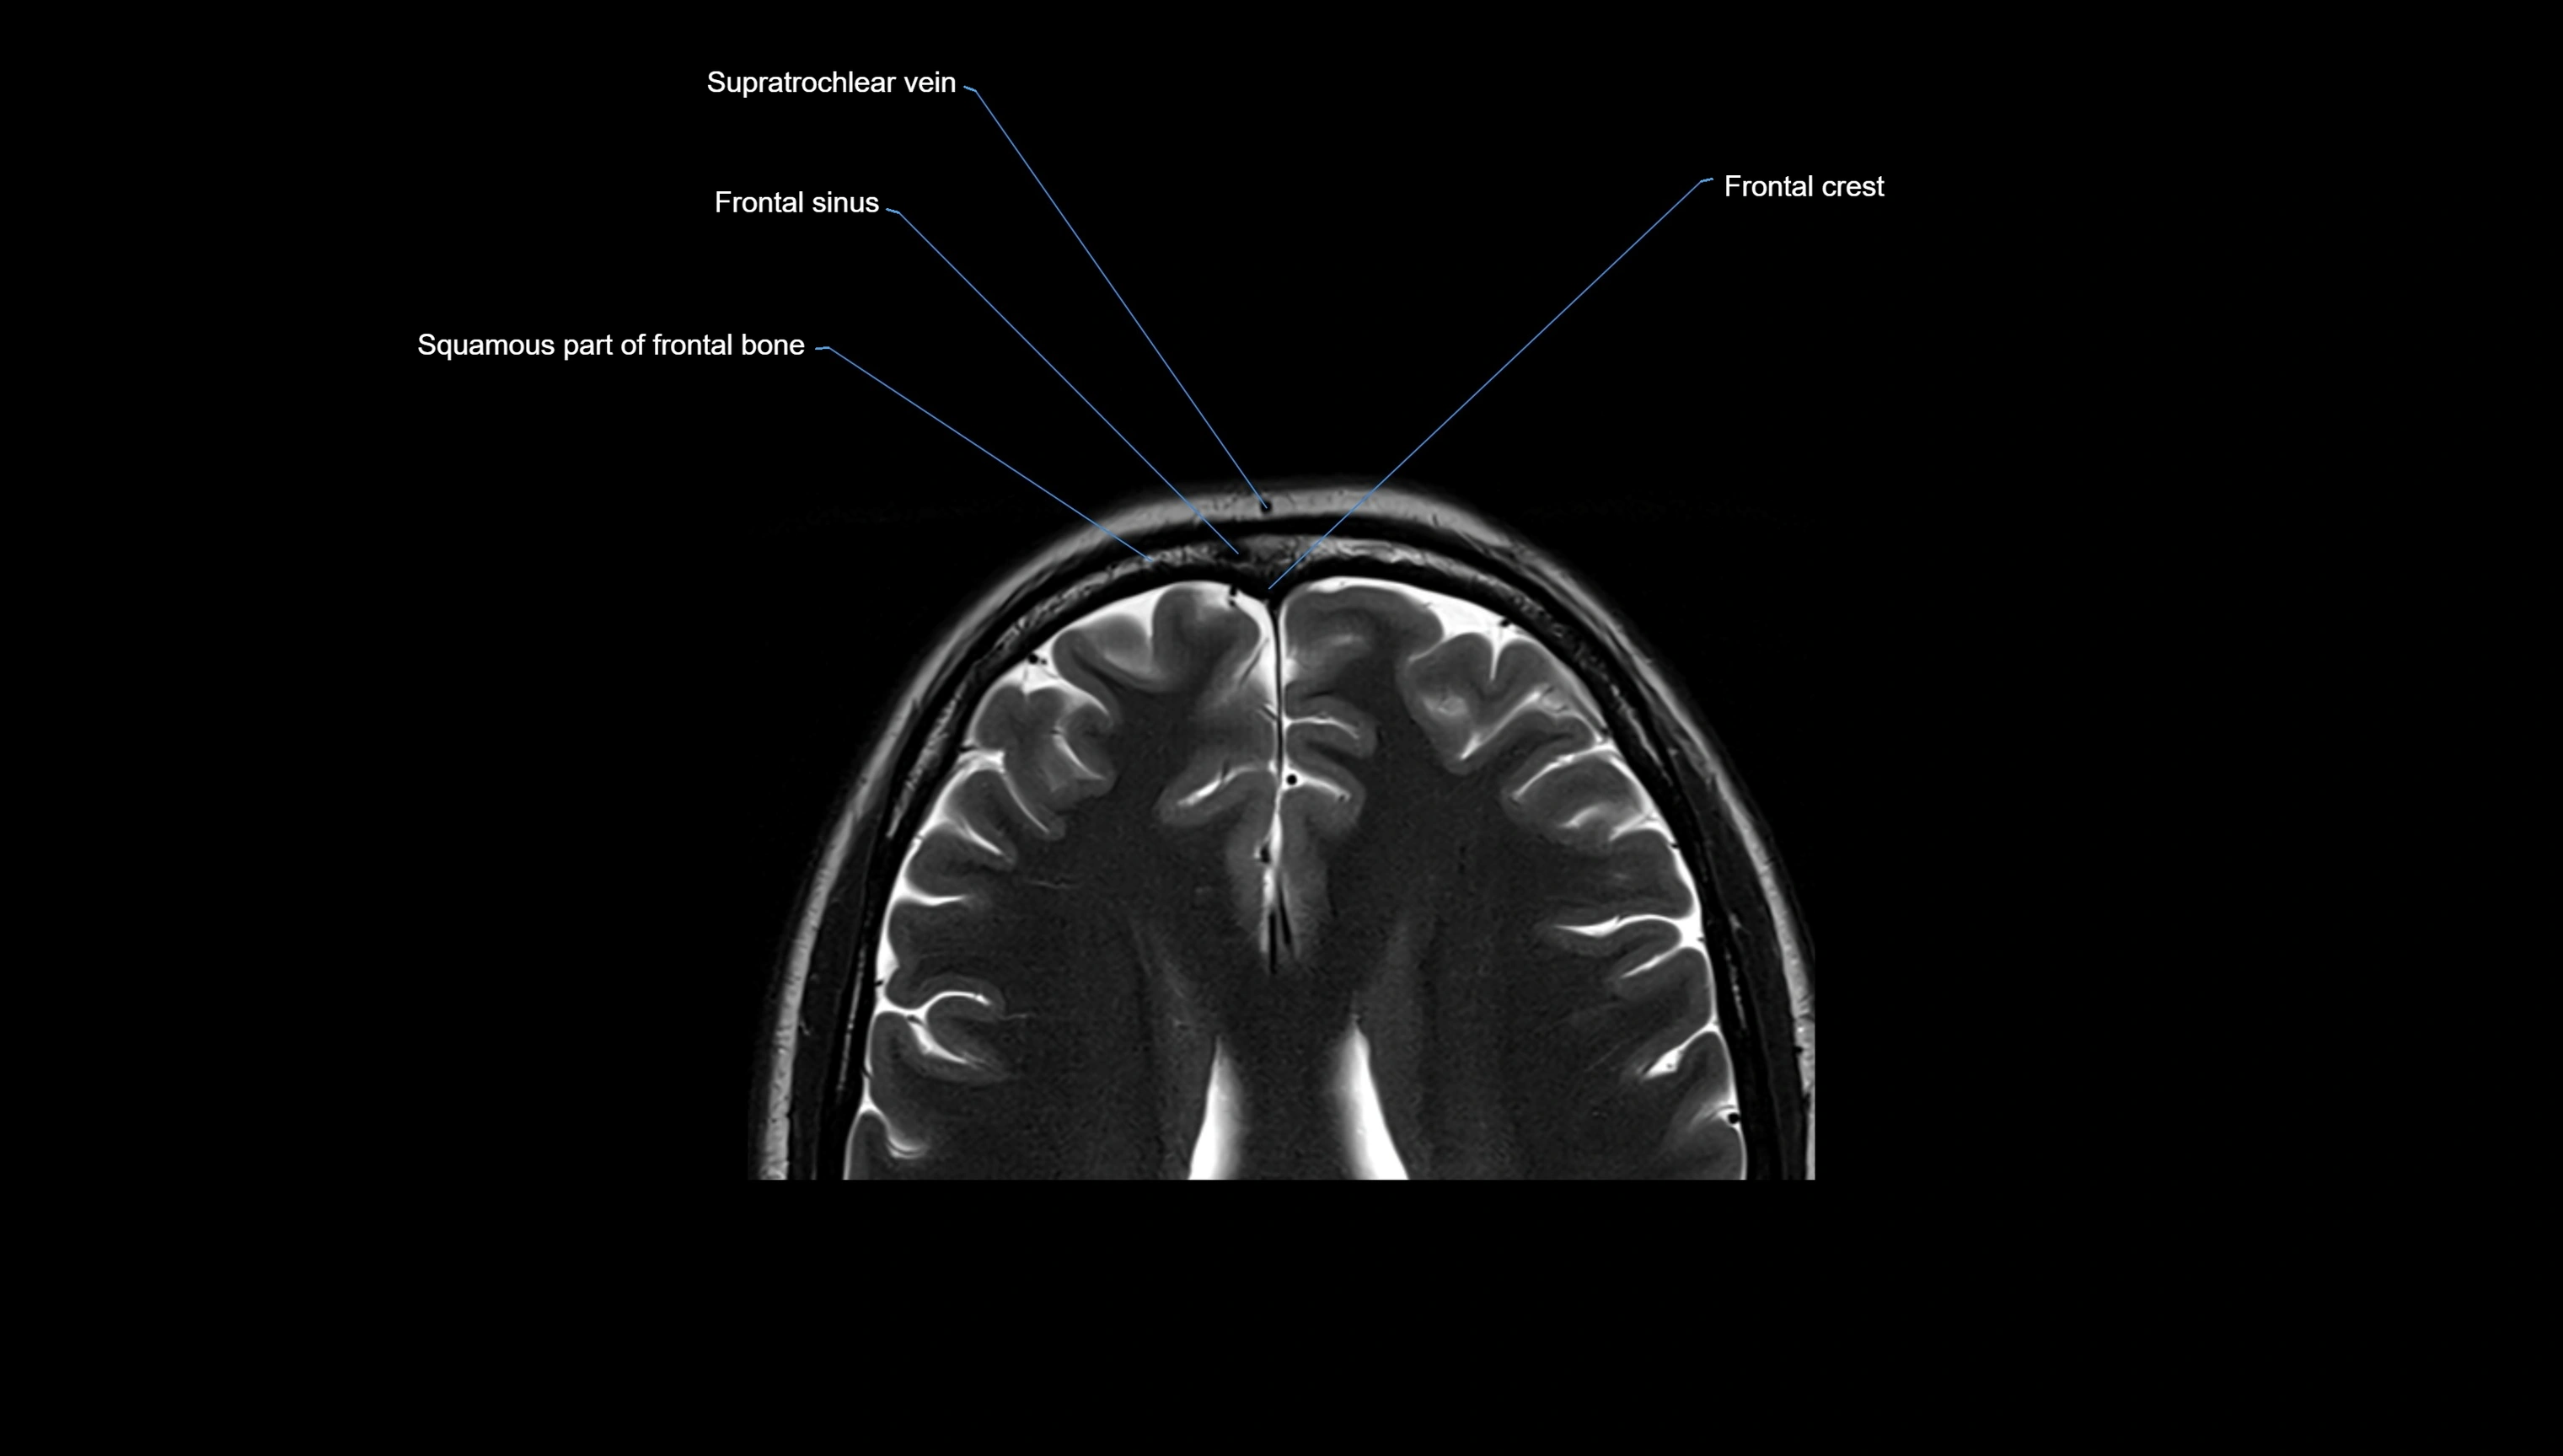

- Frontal sinus

- Supratrochlear vein